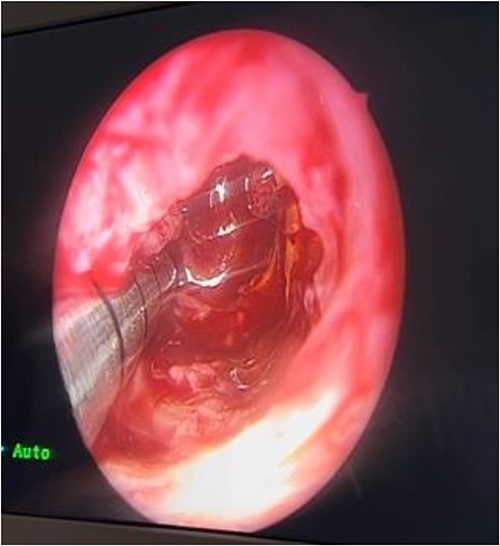

In the operating room (OR), examination under general anesthesia (GA) using a rigid nasal endoscope showed a heterogenous mass in the posterior nasal septum destructing the vomer, rostrum, and sphenoid wing. The mass was evacuated by the EEA while using the navigation system. The evacuation extended posteriorly to the sphenoid sinus, laterally to the sphenoid wing, and superiorly to the skull base (Figs 3 and 4). Lastly, Doyle nasal splints were inserted bilaterally to prevent re-accumulation of a hematoma (Fig. 5). Post-operatively, NovoSeven was administered for optimization. The patient was discharged in stable condition, and 10 days later underwent removal of the splints in the OR under GA. He followed up post-operatively at the otolaryngology clinic and was doing well, with no further complaints of epistaxis.